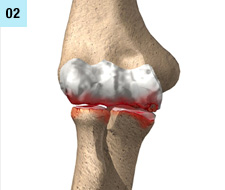

Behandlungen von Schulter-, Ellbogen- und Handgelenks-verletzungen sind oft sehr anspruchsvoll und komplex. Deshalb ist mit einer längeren Erholungsphase in vielen Fällen bis zu 6 Monaten und länger zu rechnen, beispielsweise bei Operationen bei Schulterluxationen und Instabilitäten am Schultergelenk, Schultergelenksarthroskopien bei Einklemmungssyndromen, Rekonstruktion der Rotatorenmanschette, Kunstgelenk-ersatzoperationen an der Schulter. Die Entwicklungen auf diesem Fachgebiet sind enorm vorangeschritten, sodass heute viele Eingriffe in entsprechender arthroskopischer oder minimal-invasiver Technik durchgeführt werden können. Dies führt in der Regel zu bedeutend kürzeren Spitalaufenthalten und schnellerer Erholung.

Die  wichtigsten Verletzungen und Erkrankungen an Schulter, Ellbogen und Hand: